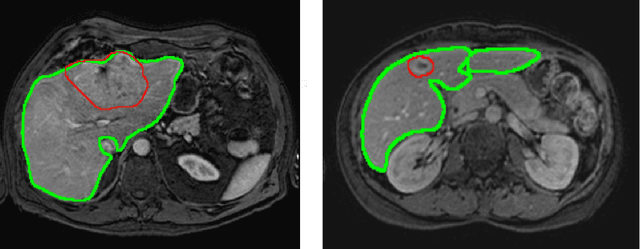

Abstract:Primary tumors have a high likelihood of developing metastases in the liver and early detection of these metastases is crucial for patient outcome. We propose a method based on convolutional neural networks (CNN) to detect liver metastases. First, the liver was automatically segmented using the six phases of abdominal dynamic contrast enhanced (DCE) MR images. Next, DCE-MR and diffusion weighted (DW) MR images are used for metastases detection within the liver mask. The liver segmentations have a median Dice similarity coefficient of 0.95 compared with manual annotations. The metastases detection method has a sensitivity of 99.8% with a median of 2 false positives per image. The combination of the two MR sequences in a dual pathway network is proven valuable for the detection of liver metastases. In conclusion, a high quality liver segmentation can be obtained in which we can successfully detect liver metastases.

Abstract:Most MRI liver segmentation methods use a structural 3D scan as input, such as a T1 or T2 weighted scan. Segmentation performance may be improved by utilizing both structural and functional information, as contained in dynamic contrast enhanced (DCE) MR series. Dynamic information can be incorporated in a segmentation method based on convolutional neural networks in a number of ways. In this study, the optimal input configuration of DCE MR images for convolutional neural networks (CNNs) is studied. The performance of three different input configurations for CNNs is studied for a liver segmentation task. The three configurations are I) one phase image of the DCE-MR series as input image; II) the separate phases of the DCE-MR as input images; and III) the separate phases of the DCE-MR as channels of one input image. The three input configurations are fed into a dilated fully convolutional network and into a small U-net. The CNNs were trained using 19 annotated DCE-MR series and tested on another 19 annotated DCE-MR series. The performance of the three input configurations for both networks is evaluated against manual annotations. The results show that both neural networks perform better when the separate phases of the DCE-MR series are used as channels of an input image in comparison to one phase as input image or the separate phases as input images. No significant difference between the performances of the two network architectures was found for the separate phases as channels of an input image.